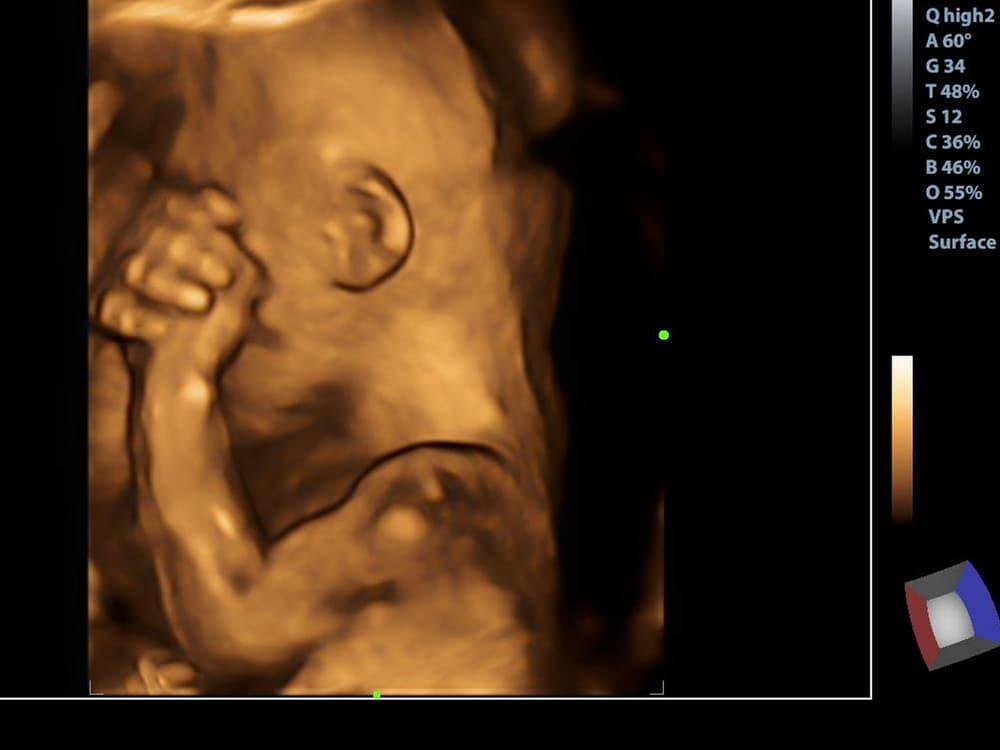

Prosedur USG 3 atau 4 dimensi membantu dokter melihat bentuk mata, hidung, telinga, serta mulut janin dengan lebih jelas. Tidak lagi sekadar gambar hitam putih seperti pada USG 2D.

Kedua jenis USG ini menghasilkan banyak gambar dari sudut berbeda yang disatukan menjadi tiga dimensi. Hal ini membantu dokter mengamati kondisi bayi secara lebih mendetail.

Secara umum, USG 3 dimensi menyajikan gambar yang tidak bergerak alias diam. Hasil jenis USG ini memiliki prinsip dasar yang sama dengan 2D, tetapi dengan banyak gambar dari sudut berbeda.

Hasilnya pun bukan gambar hitam putih seperti USG 2D, melainkan lebih mirip foto asli.

Sementara itu, hasil USG 4 dimensi menggunakan sejumlah gambar 3D yang disatukan sehingga bisa membentuk sebuah video dengan resolusi rendah.

USG 4D ini menghasilkan gambar bergerak secara real time sehingga Anda seakan menonton film yang memperlihatkan calon bayi Anda dalam kandungan.

Melalui USG 4D, Anda dapat melihat apa saja yang janin lakukan di dalam kandungan, seperti menguap, mengisap jempol, atau menendang.